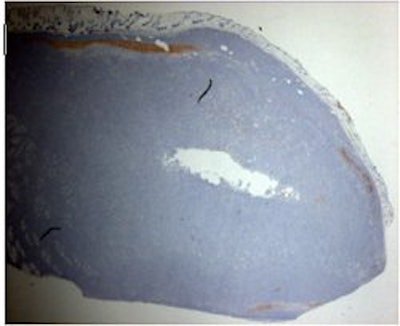

Above, ultrasound image of NHL xenograft done on a 20-MHz transducer at 24 hours after CHOP chemotherapy. The apoptotic areas correspond to the areas of high-intensity backscatter. Below, corresponding histology image with TUNEL stain. The areas that are stained brown correspond to the apoptotic areas. Images courtesy of Dr. Charles Cho.

For the study led by Cho, NHL tumors were placed in severe combined immunodeficiency disease (SCID) mice. These tumor-bearing animals were then treated with single doses of 8 Gy or with one to two cycles of cyclophosphamide, hydroxydaunomycin, vincristine, and prednisone (CHOP) chemotherapy.

The animals were then imaged with 20-MHz spectroscopic ultrasound (VS40B, VisualSonics, Toronto). For the 26 mice that had chemotherapy, imaging was done several times, five to 72 hours after treatment. For the eight mice that had radiotherapy, sonography was performed once, six hours after treatment. Tumor sections were terminal transferase dUTP nick end labeling (TUNEL) stained to confirmed apoptotic cell death.

The authors found a time-dependent increase in backscatter following CHOP chemotherapy, they wrote in their results. The measured high-intensity (10-decibel increase) patch areas on ultrasound were 1.76 mm² at five hours, 0.27 mm² at 12 hours, 2.03 mm² at 24 hours, 2.93 mm² at 48 hours, and 0.12 mm² at 72 hours.

Based on spectroscopy results, the midband fits changes from -51 dBr to -44 dBr after chemotherapy. The spectral slope was invariant at 0.66 dBr/MHz pretreatment and -0.60 dBr/MHz at 48 hours post-treatment.

"Image analysis demonstrated a correlation between the size of high-intensity patches on high-frequency ultrasound and immunohistochemical TUNEL staining or apoptotic areas," the group wrote.